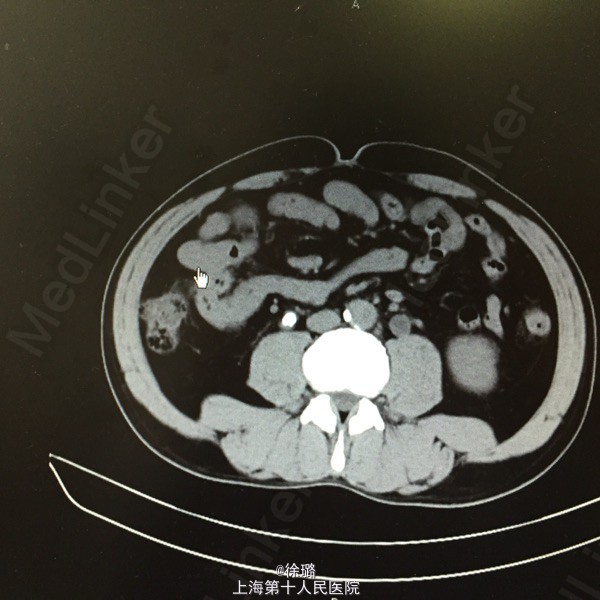

患者XXX,男,52岁。 主述:腰部酸胀不适半年余。 病史:患者半年前始无明显诱因出现腰部酸胀不适,左侧腰部酸胀稍明显,无恶心呕吐,不伴发热、黄疸、腹泻、黑便及肉眼血尿,症状轻,未诊治,今患者至当地医院查体,查B超示:双侧输尿管扩张伴肾积水,双侧输尿管上段结石。患者为进一步治疗,来我院就诊,拟“双侧输尿管上段结石”收住入院。

查体:双肾区无明显膨隆,左肾区无明显压痛,叩击痛可疑阳性,右肾区无明显压痛,叩击痛阴性,左侧输尿管走行区下段叩击痛阳性,右侧输尿管走行区下段叩击痛阴性,膀胱区无充盈,无压痛,尿道口无红肿。前列腺指检:前列腺未及增大,质韧,无明显结节,压痛阴性,指套无血染。 辅检:B超示:双侧输尿管扩张伴肾积水,双侧输尿管上段结石。尿路平片:1.双侧输尿管上段走行区致密影,考虑输尿管结石可能。2:盆腔耻骨联合上方投影区钙化影,前列腺钙化?请结合其他检查。3.CT:两侧输尿管上段结石,致其上输尿管及肾盂肾盏明显扩张积液。